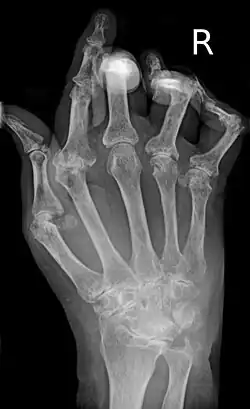

X-ray of the hand in rheumatoid arthritis

X-rays of the hands and feet are generally performed when many joints are affected. In RA, there may be no changes in the early stages of the disease, or the X-ray may show osteopenia near the joint, soft tissue swelling, and a smaller than normal joint space. As the disease advances, there may be bony erosions and subluxation. Other medical imaging techniques such as magnetic resonance imaging (MRI) and ultrasound are also used in RA.[20][80]

Technical advances in ultrasonography, like high-frequency transducers (10 MHz or higher), have improved the spatial resolution of ultrasound images, depicting 20% more erosions than conventional radiography. Color Doppler and power Doppler ultrasound are useful in assessing the degree of synovial inflammation as they can show vascular signals of active synovitis. This is important since in the early stages of RA, the synovium is primarily affected, and synovitis seems to be the best predictive marker of future joint damage.[81]